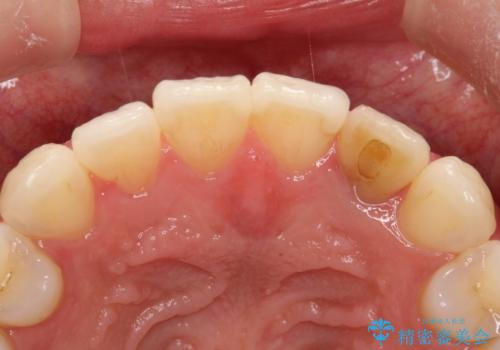

前歯の変色 オールセラミッククラウン

- 前歯の変色を主訴に来院されました。

根管治療後、オールセラミッククラウン(エクセレント)にて治療を行なっています。